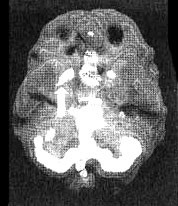

Марша — медицинская сестра, которую привез к нам ее муж. Первый приступ паники случился с ней в 36 лет. Она покупала продукты, когда вдруг у нее закружилась голова, ей стало нечем дышать, сердце заколотилось, а саму ее охватило ощущение надвигающейся беды. Она бросила тележку с покупками посреди магазина, убежала в машину и там целый час проплакала. После того раза приступы паники стали повторяться и со временем участились настолько, что она перестала выходить из дома, опасаясь, что на улице с ней случится очередной приступ и ей никто не поможет. Она оставила работу и просила мужа отвозить детей в школу и забирать их из школы. Марша отказывалась пить лекарства, так как когда-то давно у ее матери, которая тоже пыталась бороться с такими же приступами, развилась зависимость от Valium. С Маршей в то время она обращалась довольно жестоко. Марша ни в чем не желала походить на мать. Ей казалось, что она «должна» справиться с этими приступами. Ее муж, видя, что состояние жены продолжает ухудшаться, поехал с ней к семейному психологу. Тот показал ей приемы расслабления и научил отвечать неприятным мыслям. Это не помогло. Марше становилось все хуже, и тогда муж привез ее к нам. Поскольку Марша отказывалась принимать лекарства, я назначил исследование SPECT, чтобы оценить ее состояние и наглядно показать ей, что происходит с ее мозгом. Результаты сканирования выявили повышенную очаговую активность правого базального узла — довольно частое состояние у пациентов, страдающих приступами паники. Любопытно, что у больных судорожным синдромом также наблюдаются очаги повышенной активности мозга. В силу того, что приступ паники сопровождается бурными эмоциональными переживаниями, мы с коллегами пытаемся понять, насколько то, что мы узнали о функциях базальных ганглиев, справедливо для случаев поведенческих судорог.

Мозг Марты — паническое расстройство

Трехмерное изображение — активный мозг, вид снизу. Обратите внимание на повышенную активность базальных ганглиев справа (помечено стрелкой).